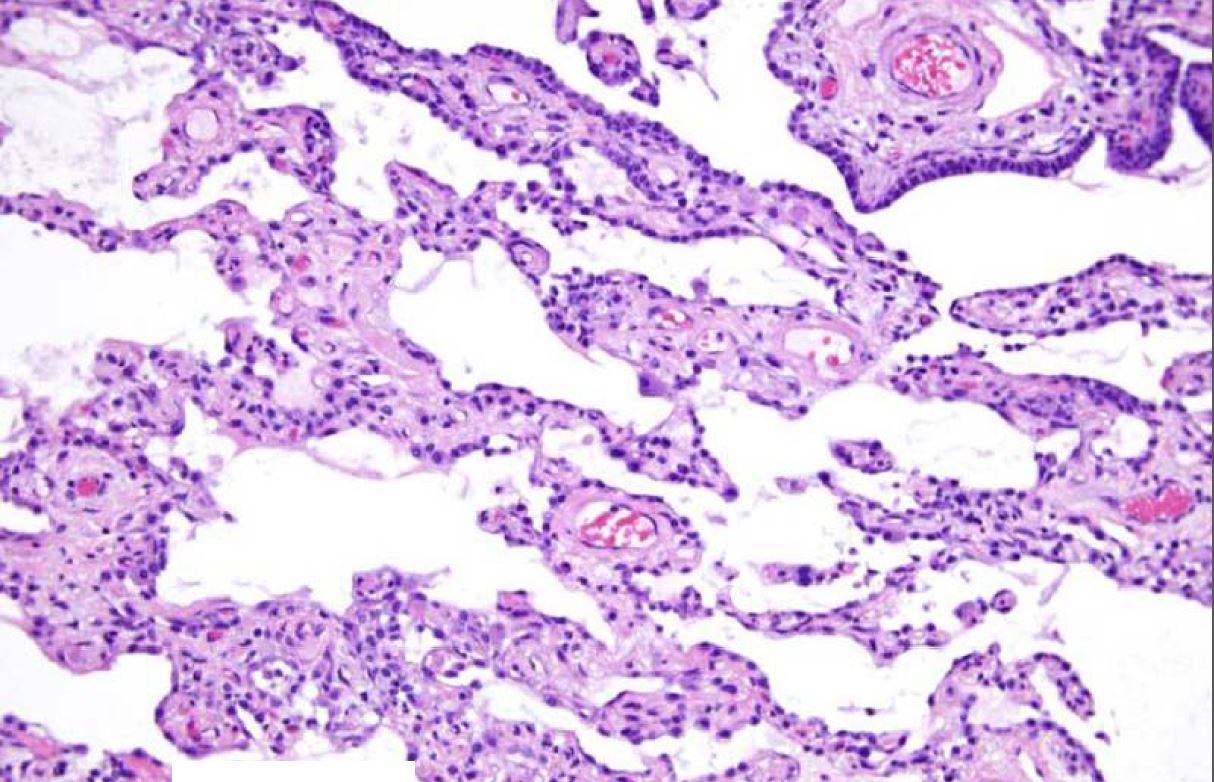

What process is being shown here?

Hallmarks are lower lobes and peripheral/paraseptal

accentuation of changes

UIP